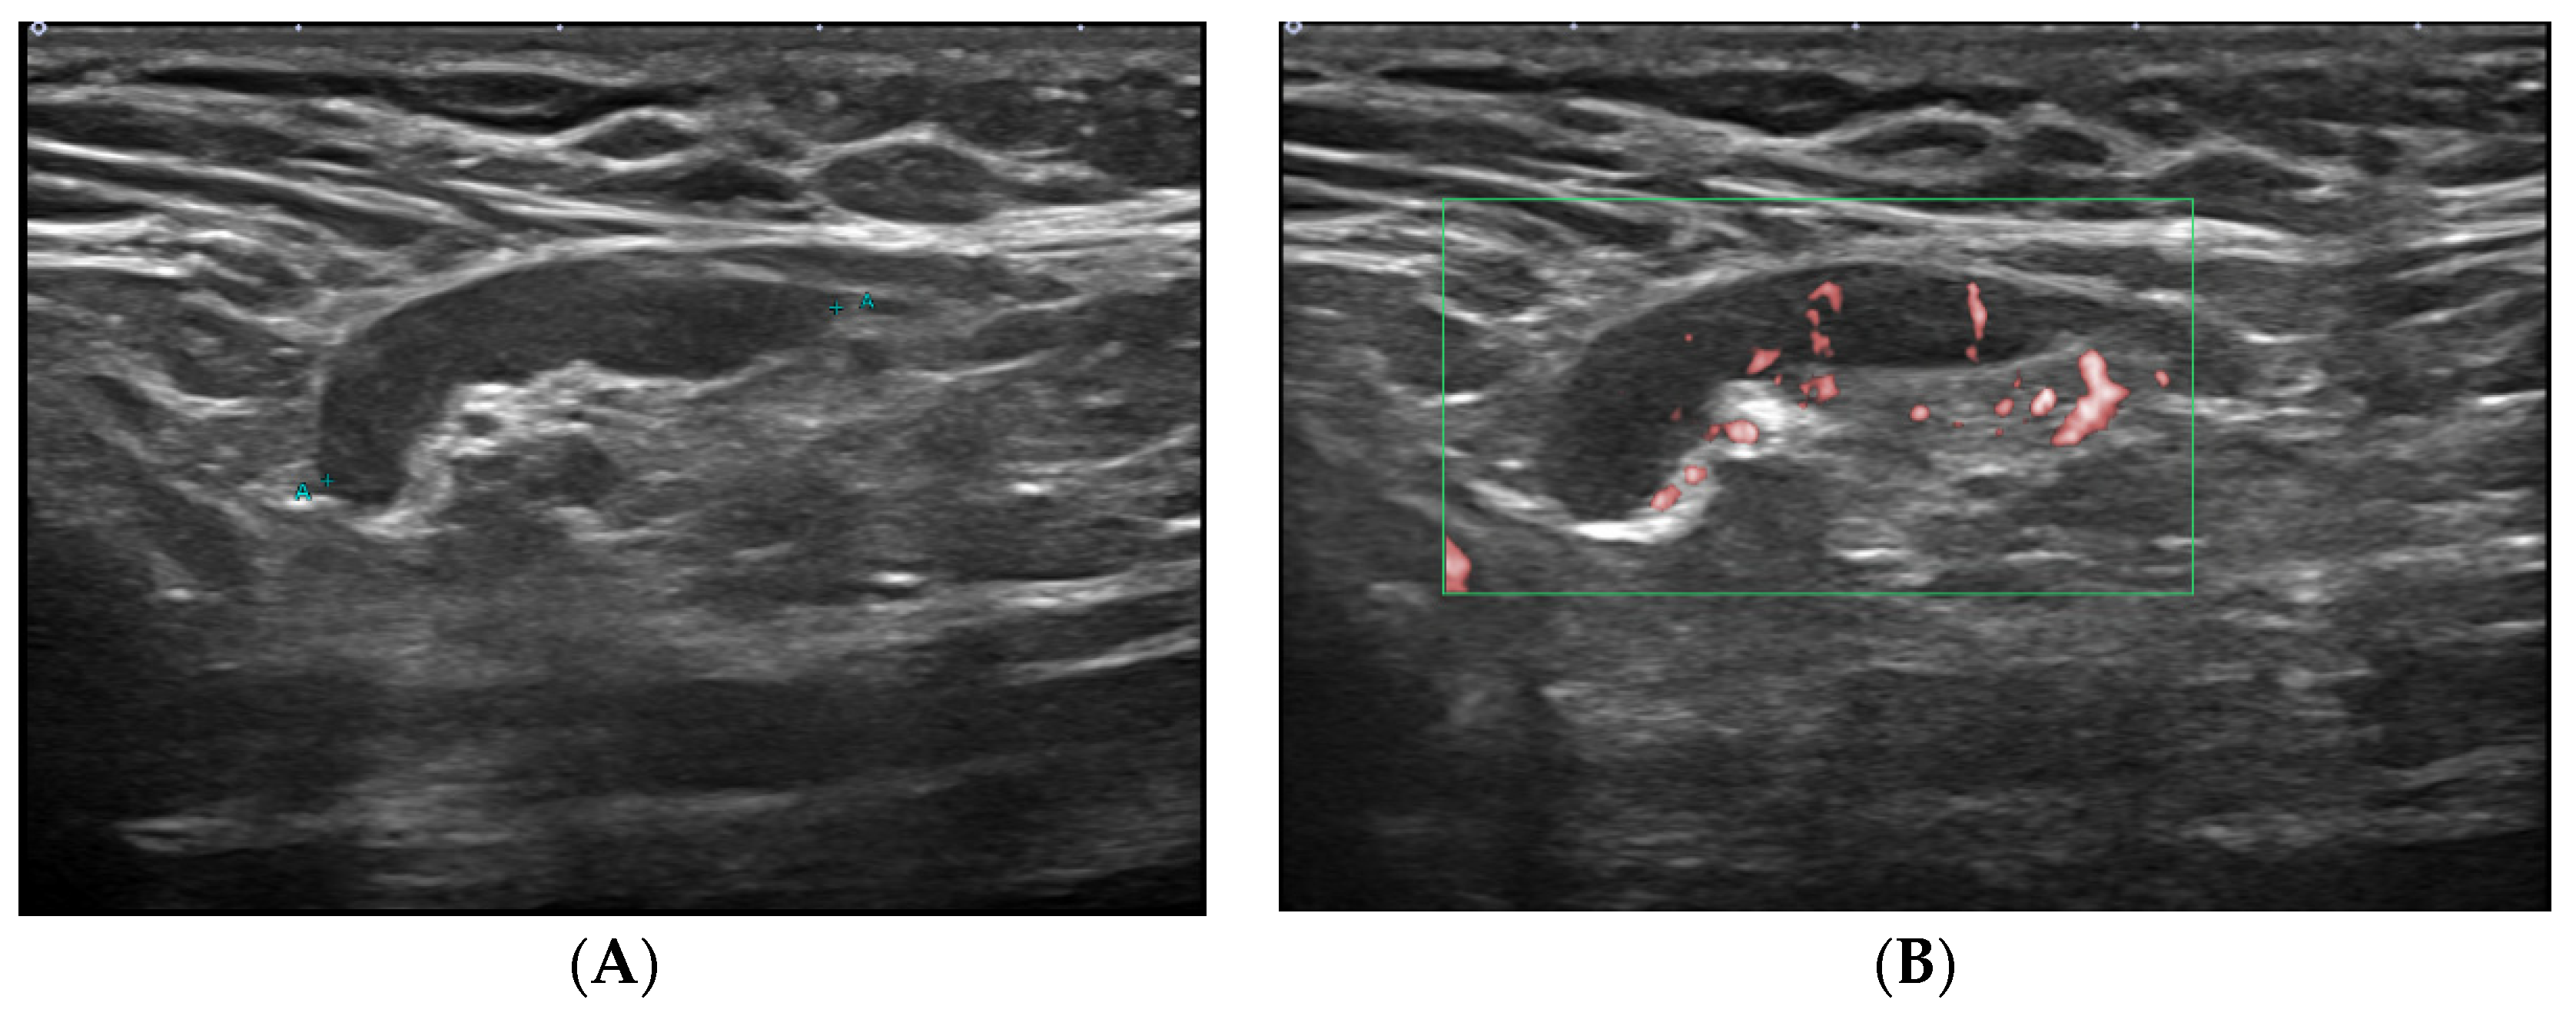

2.2. Ultrasound Technique